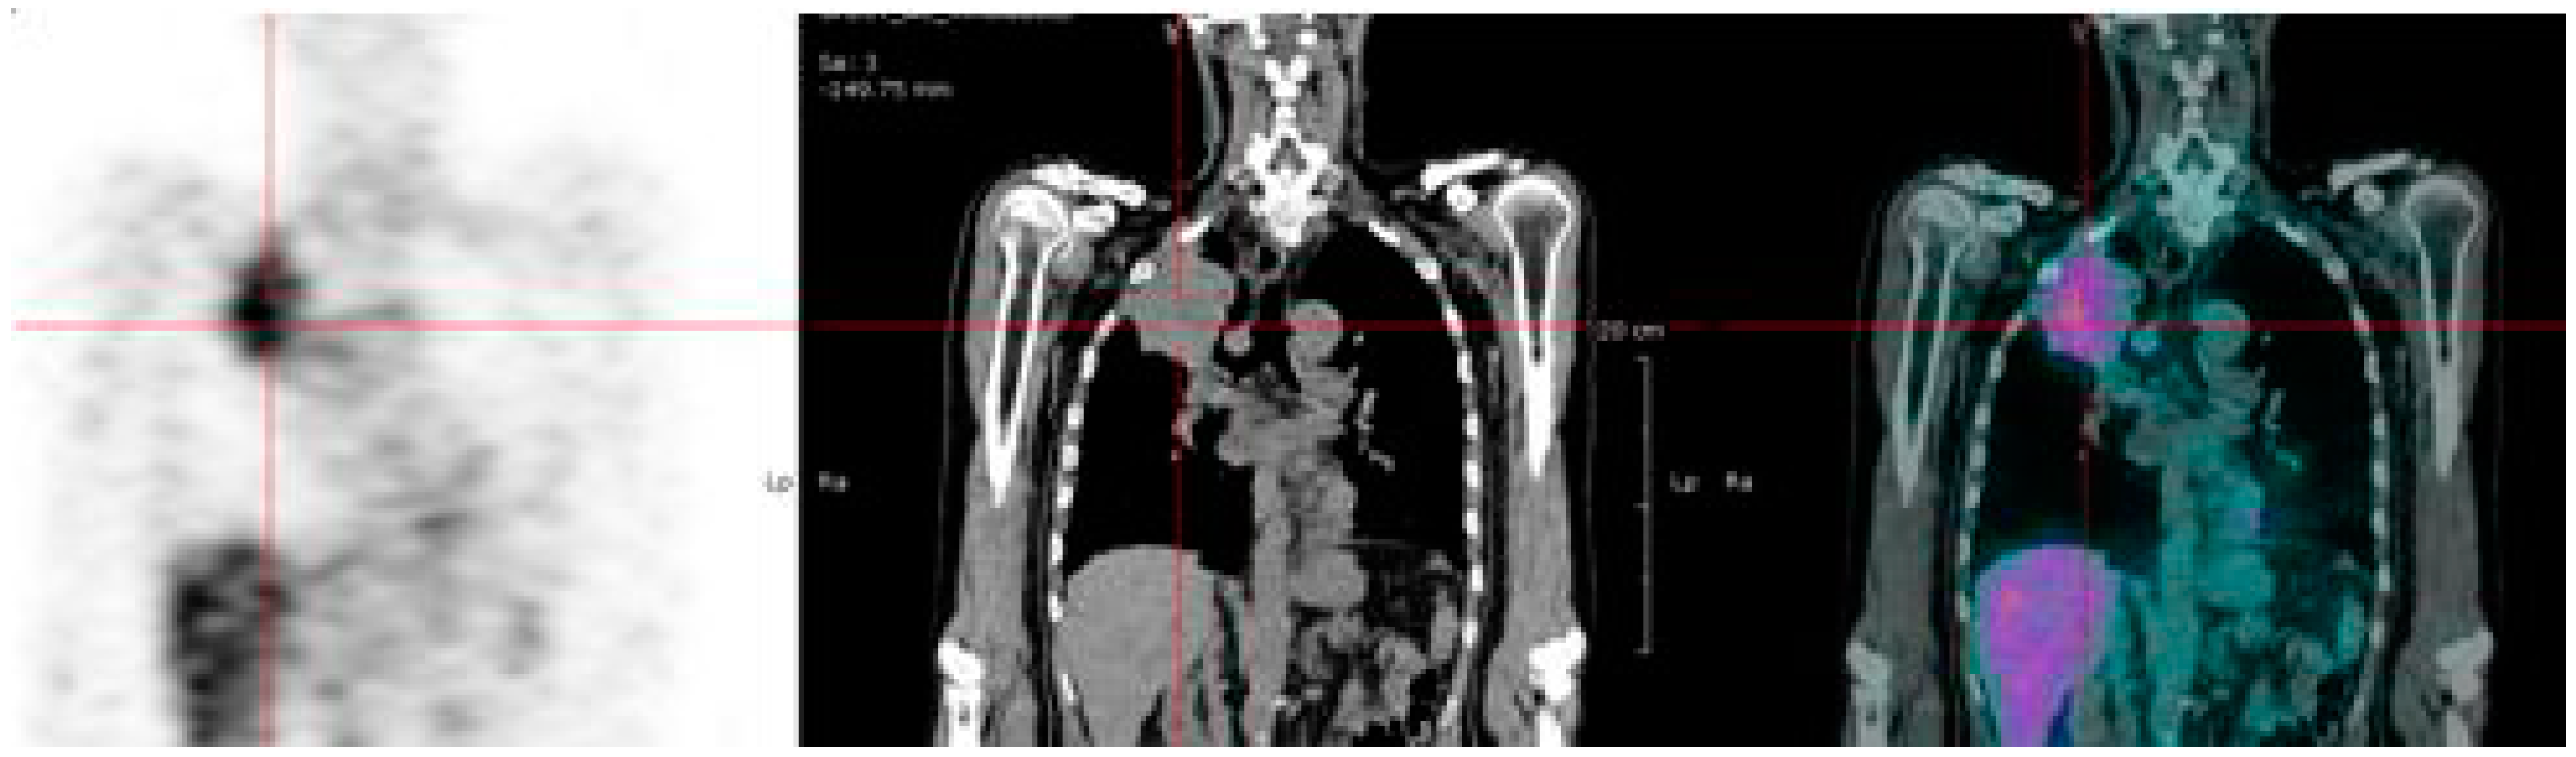

6.2. 68Ga-Peptide for Pretargeted Immuno-PET in CEA Positive Tumors